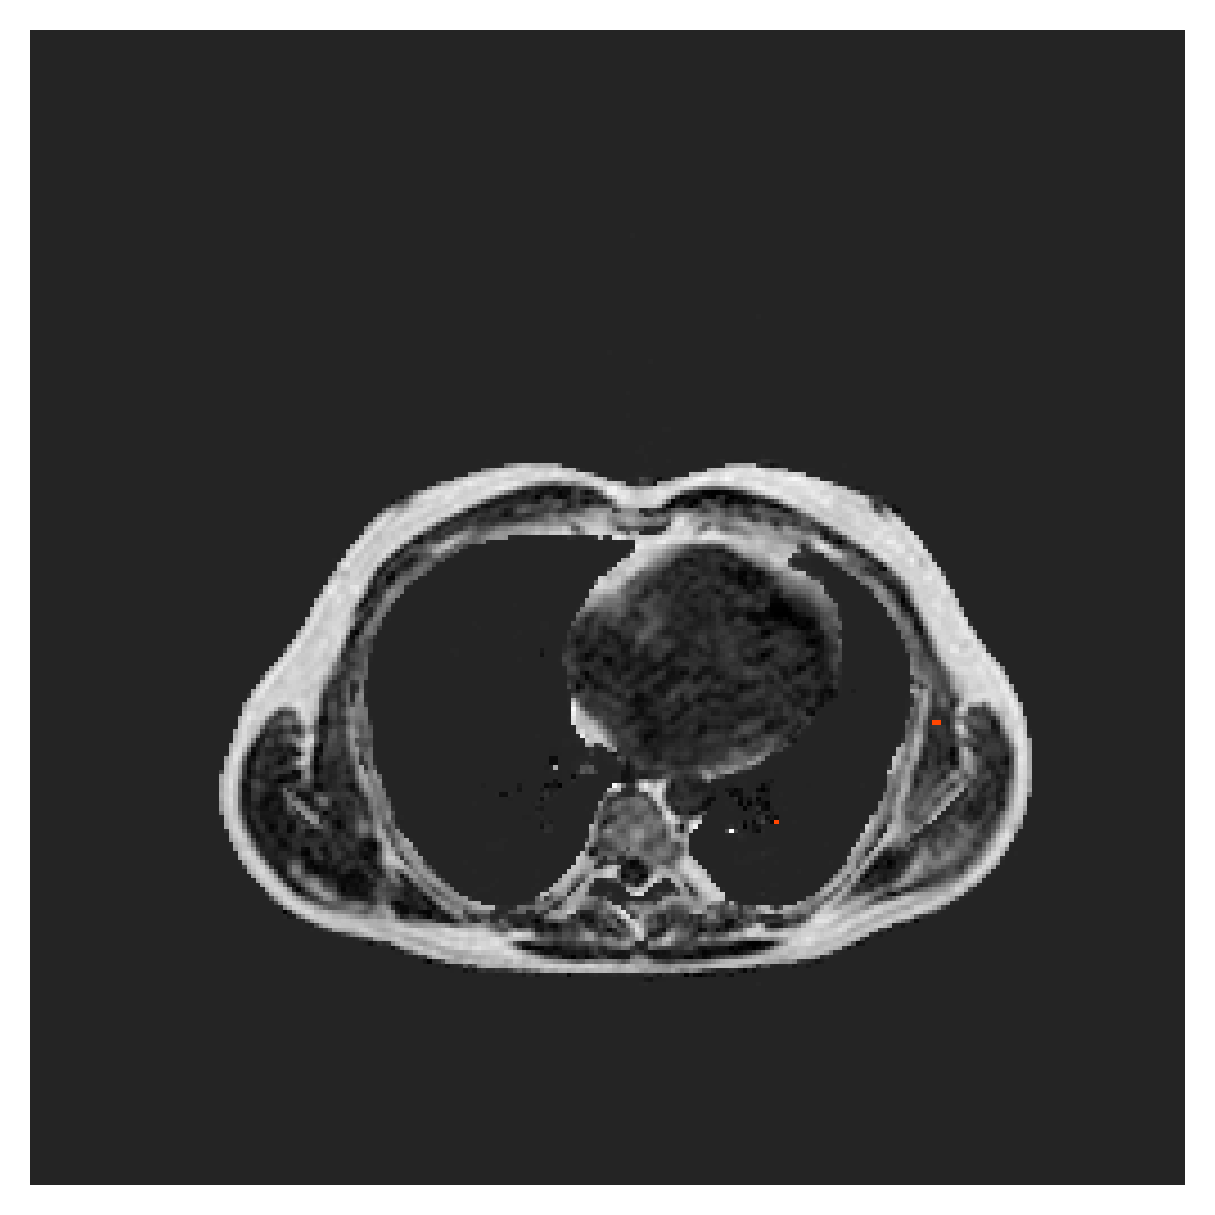

([5]) The Automated Cardiac Diagnosis Challenge (ACDC) is a public benchmark multi-class heart segmentation dataset. It contains cine-MR images of 150 patients (of which 100 are available for training and the rest 50 comprise a test set), covering healthy scans and four types of pathologies in equal amounts, with annotations for the right ventricle (RV), myocardium (Myo) and left ventricle (LV) heart structures. We split the training set randomly, using 65 subjects for training, 10 for validation and 25 as a hold-out test set. Due to the large and varying interslice gap, we work with 2D slices instead of 3D volumes directly. This includes distance map computation.

We normalize the volumes and resize the slices to pixels. As the official dataset comes with full annotations, we create a synthetic point ground truth. This is done by first randomly choosing the centers of the point annotations within the class masks, followed by filling an ellipse with axes lengths of and (in pixels) around each center. The intersections of these elliptic discs with the underlying full annotations are then used as our point ground truth. See Figure 2 for an example of the created weak annotation mask. The point annotations are created for every slice, one for each foreground object present in the slice.